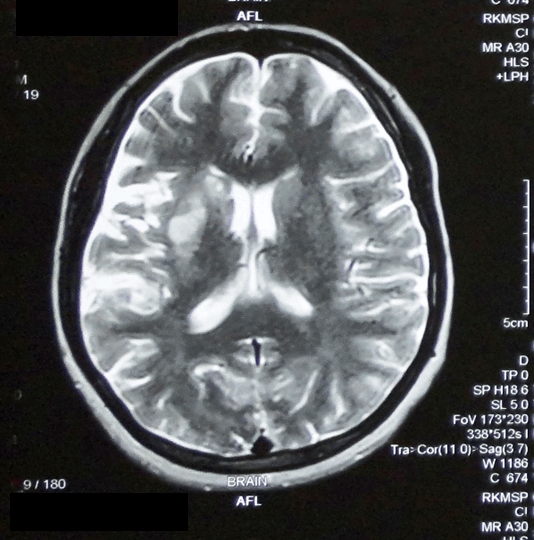

An urgent non-contrast magnetic resonance imaging scan of brain was done which showed acute infarct in right centrum semiovale and right gangliocapsular region in the right middle cerebral artery territory. (Figure 1) Patient’s complete hemogram, liver function tests, serum creatinine and electrolytes were normal. Abdominal ultrasound showed a single, live fetus with normal parameters. Echocardiography was normal. She had normal prothrombin and activated partial thromboplastin time. The patient was seronegative for hepatitis B, C and HIV. Antinuclear factor by indirect immunofluorescence method was negative. Anticardiolipin antibodies, antineutrophil cytoplasmic antibodies (pANCA and cANCA) were negative. Blood homocysteine level, Lupus anticoagulant screen time was normal. Mutation of factor V could not be detected by real time polymerase chain reaction. Protein C (0.9 mg/L, reference range 1.67–3.16 mg/L) and protein S (7 mg/L, reference range 55–123 mg/L) levels were low.

Figure 1: A non-contrast magnetic resonance imaging scan of brain showing an acute infarct in right centrum semiovale and right gangliocapsular region in the right middle cerebral artery territory.